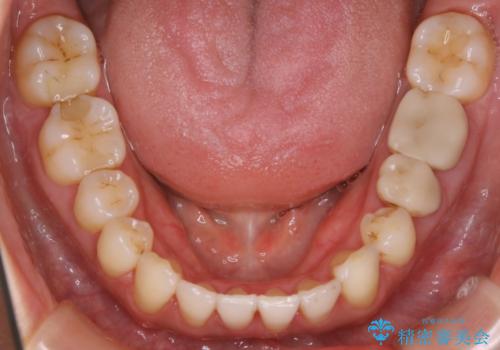

- 歯のガタつきによる見栄えや清掃困難を主訴にご来院されました。

左側の噛み合わせは上の歯が前方に寄ってきてしまっていることが原因のズレがありました。

ガタつき自体は歯列の幅の拡大やディスキング(IPR)でほとんど解消可能でしたが、噛み合わせのズレは歯の移動が必要だったため、左上にマイクロインプラントを使用し噛み合わせの改善とガタつきの解消を同時に進めるという方針をとりました。

歯列弓の拡大

歯並びが悪くなる原因の一つに「歯列弓の狭窄」というものがあります。

奥歯や前歯が内側(舌側)に倒れ込んでしまったり、歯が生えてくる位置が内側になってしまうことにより歯並びのアーチが狭くなってしまうことを言います。

このような場合、歯並びのアーチを拡大してあげるだけでもガタつきを無くすためのスペースがかなり作れることがあります。